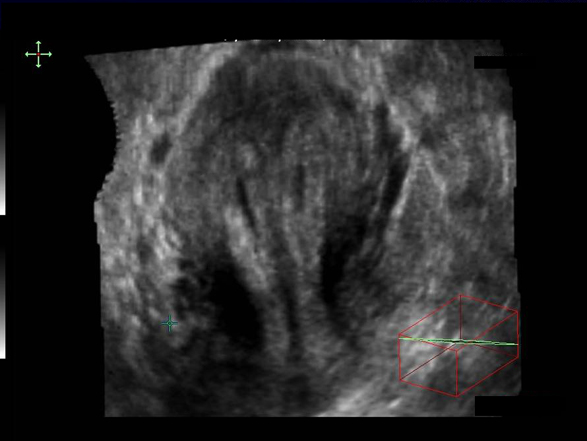

Utérus cloisonné total, même patiente hors grossesse